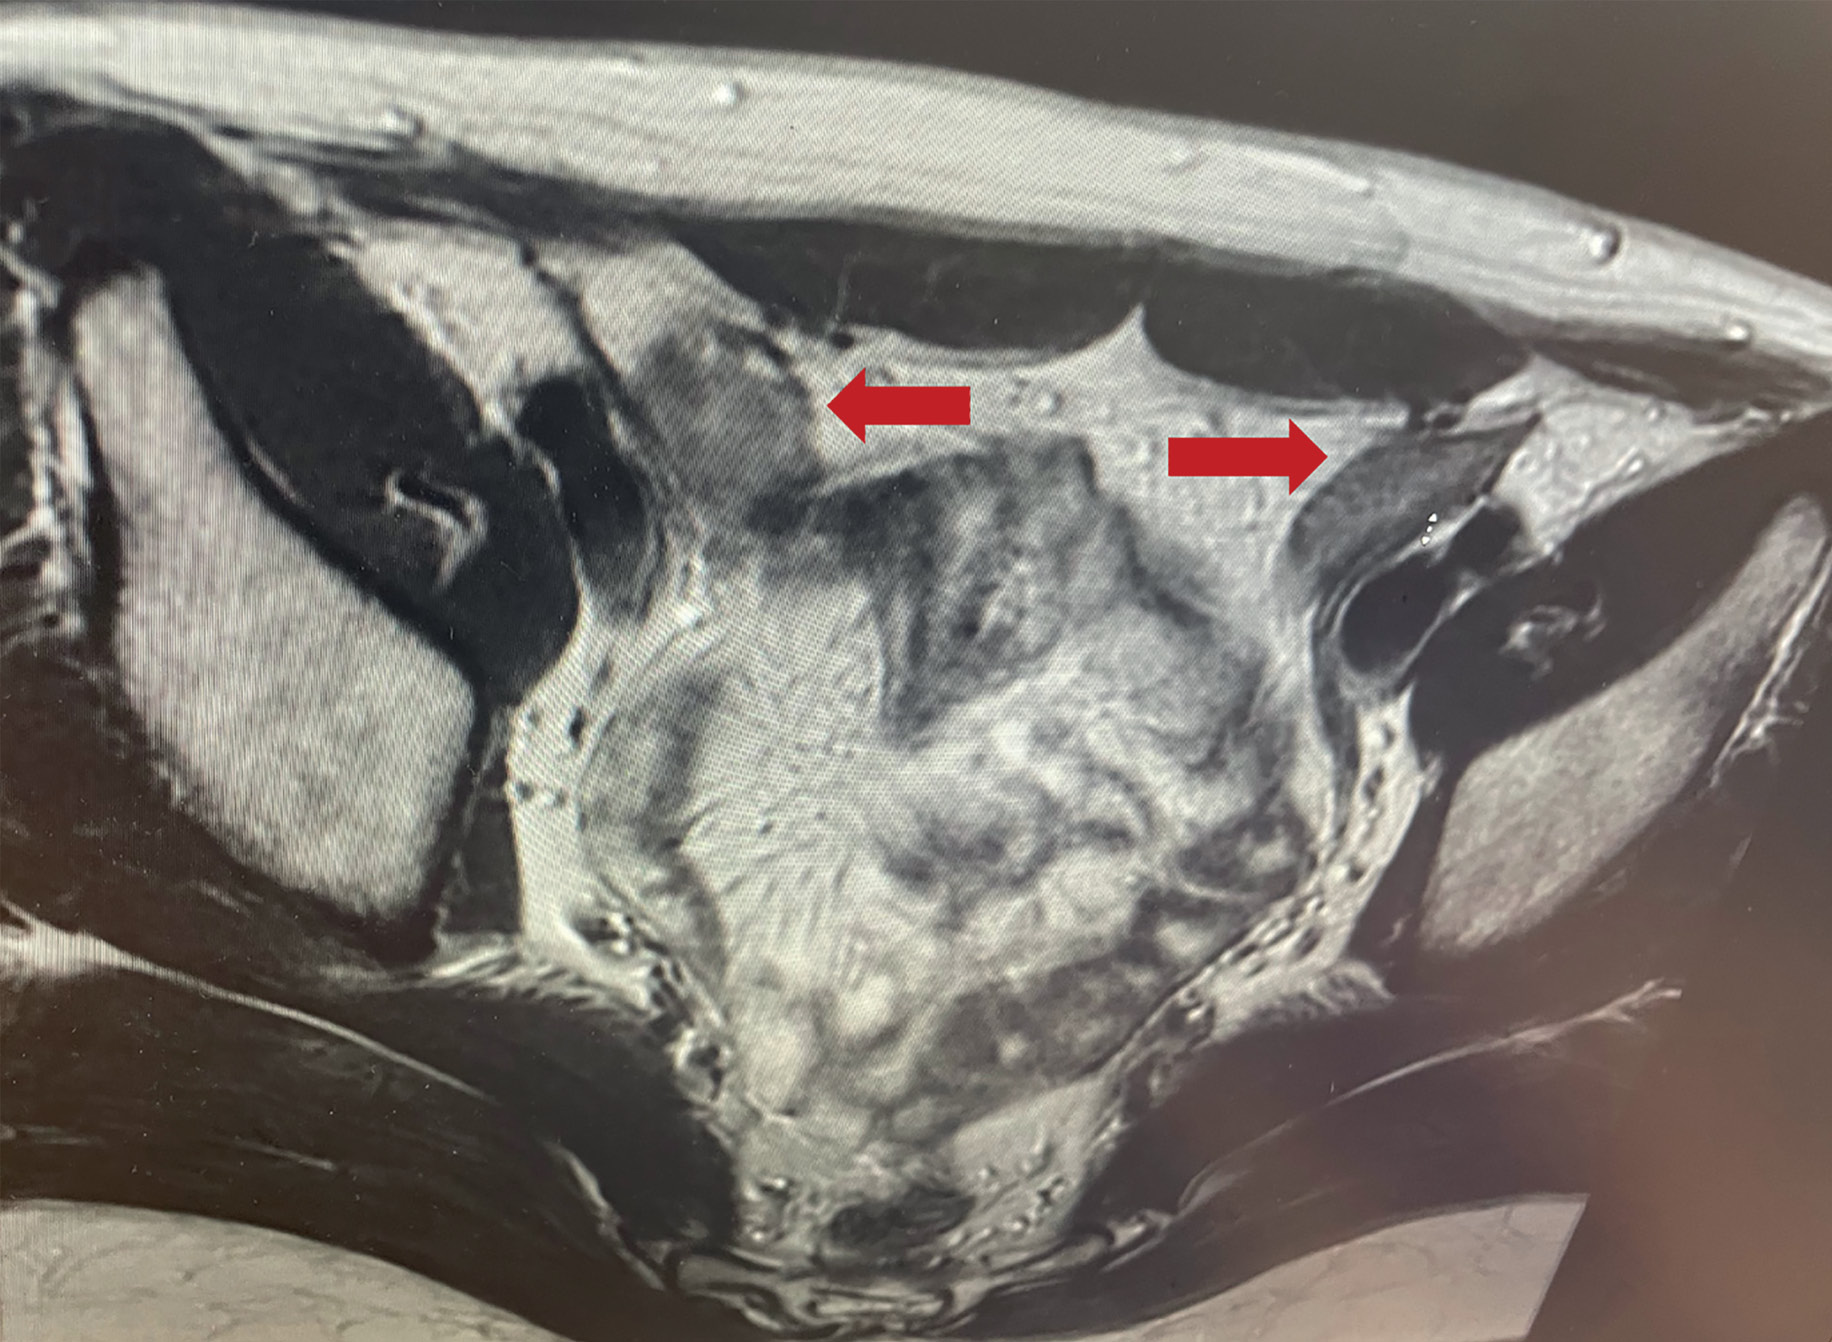

В ходе госпитализации, по данным гормонального анализа крови, выявлены изменения гормонального профиля, характерные для СТФ: повышение тестостерона до 19,4 нмоль/л (норма — до 2,7), ЛГ — до 28,9 Ед/л, нормальные значения ФСГ (2,06 Ед/л) и эстрадиола — 135,7 пмоль/л. При МРТ органов малого таза визуализировались признаки гонад (яичек): в правой подвздошной области размерами 23х20х38 мм, с четкими неровными контурами, неоднородной структуры, с признаками накопления контрастного препарата; также справа — зона размерами 26х23х28 мм, с кистозными включениями; в левой подвздошной области определяется структура овальной формы, размерами около 32х14х29 мм, с четкими неровными контурами, неоднородной структуры, с признаками накопления контрастного препарата; МР-признаки аплазии матки и шейки матки (рис. 1). С целью исключения остеопороза на фоне основного заболевания выполнена рентгеновская остеоденситометрия поясничного отдела позвоночника и проксимального отдела бедренной кости, по данным которой снижения минеральной плотности костей не выявлено.

Рисунок 1. МРТ органов малого таза. Стрелки указывают на гонады (яички) в паховом канале.

Figure 1. MRI of the pelvic organs. Arrows indicate the gonads (testes) in the inguinal canal.